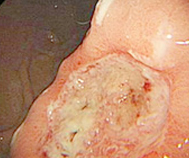

在郑州益好医院治愈的萎缩性胃炎患者